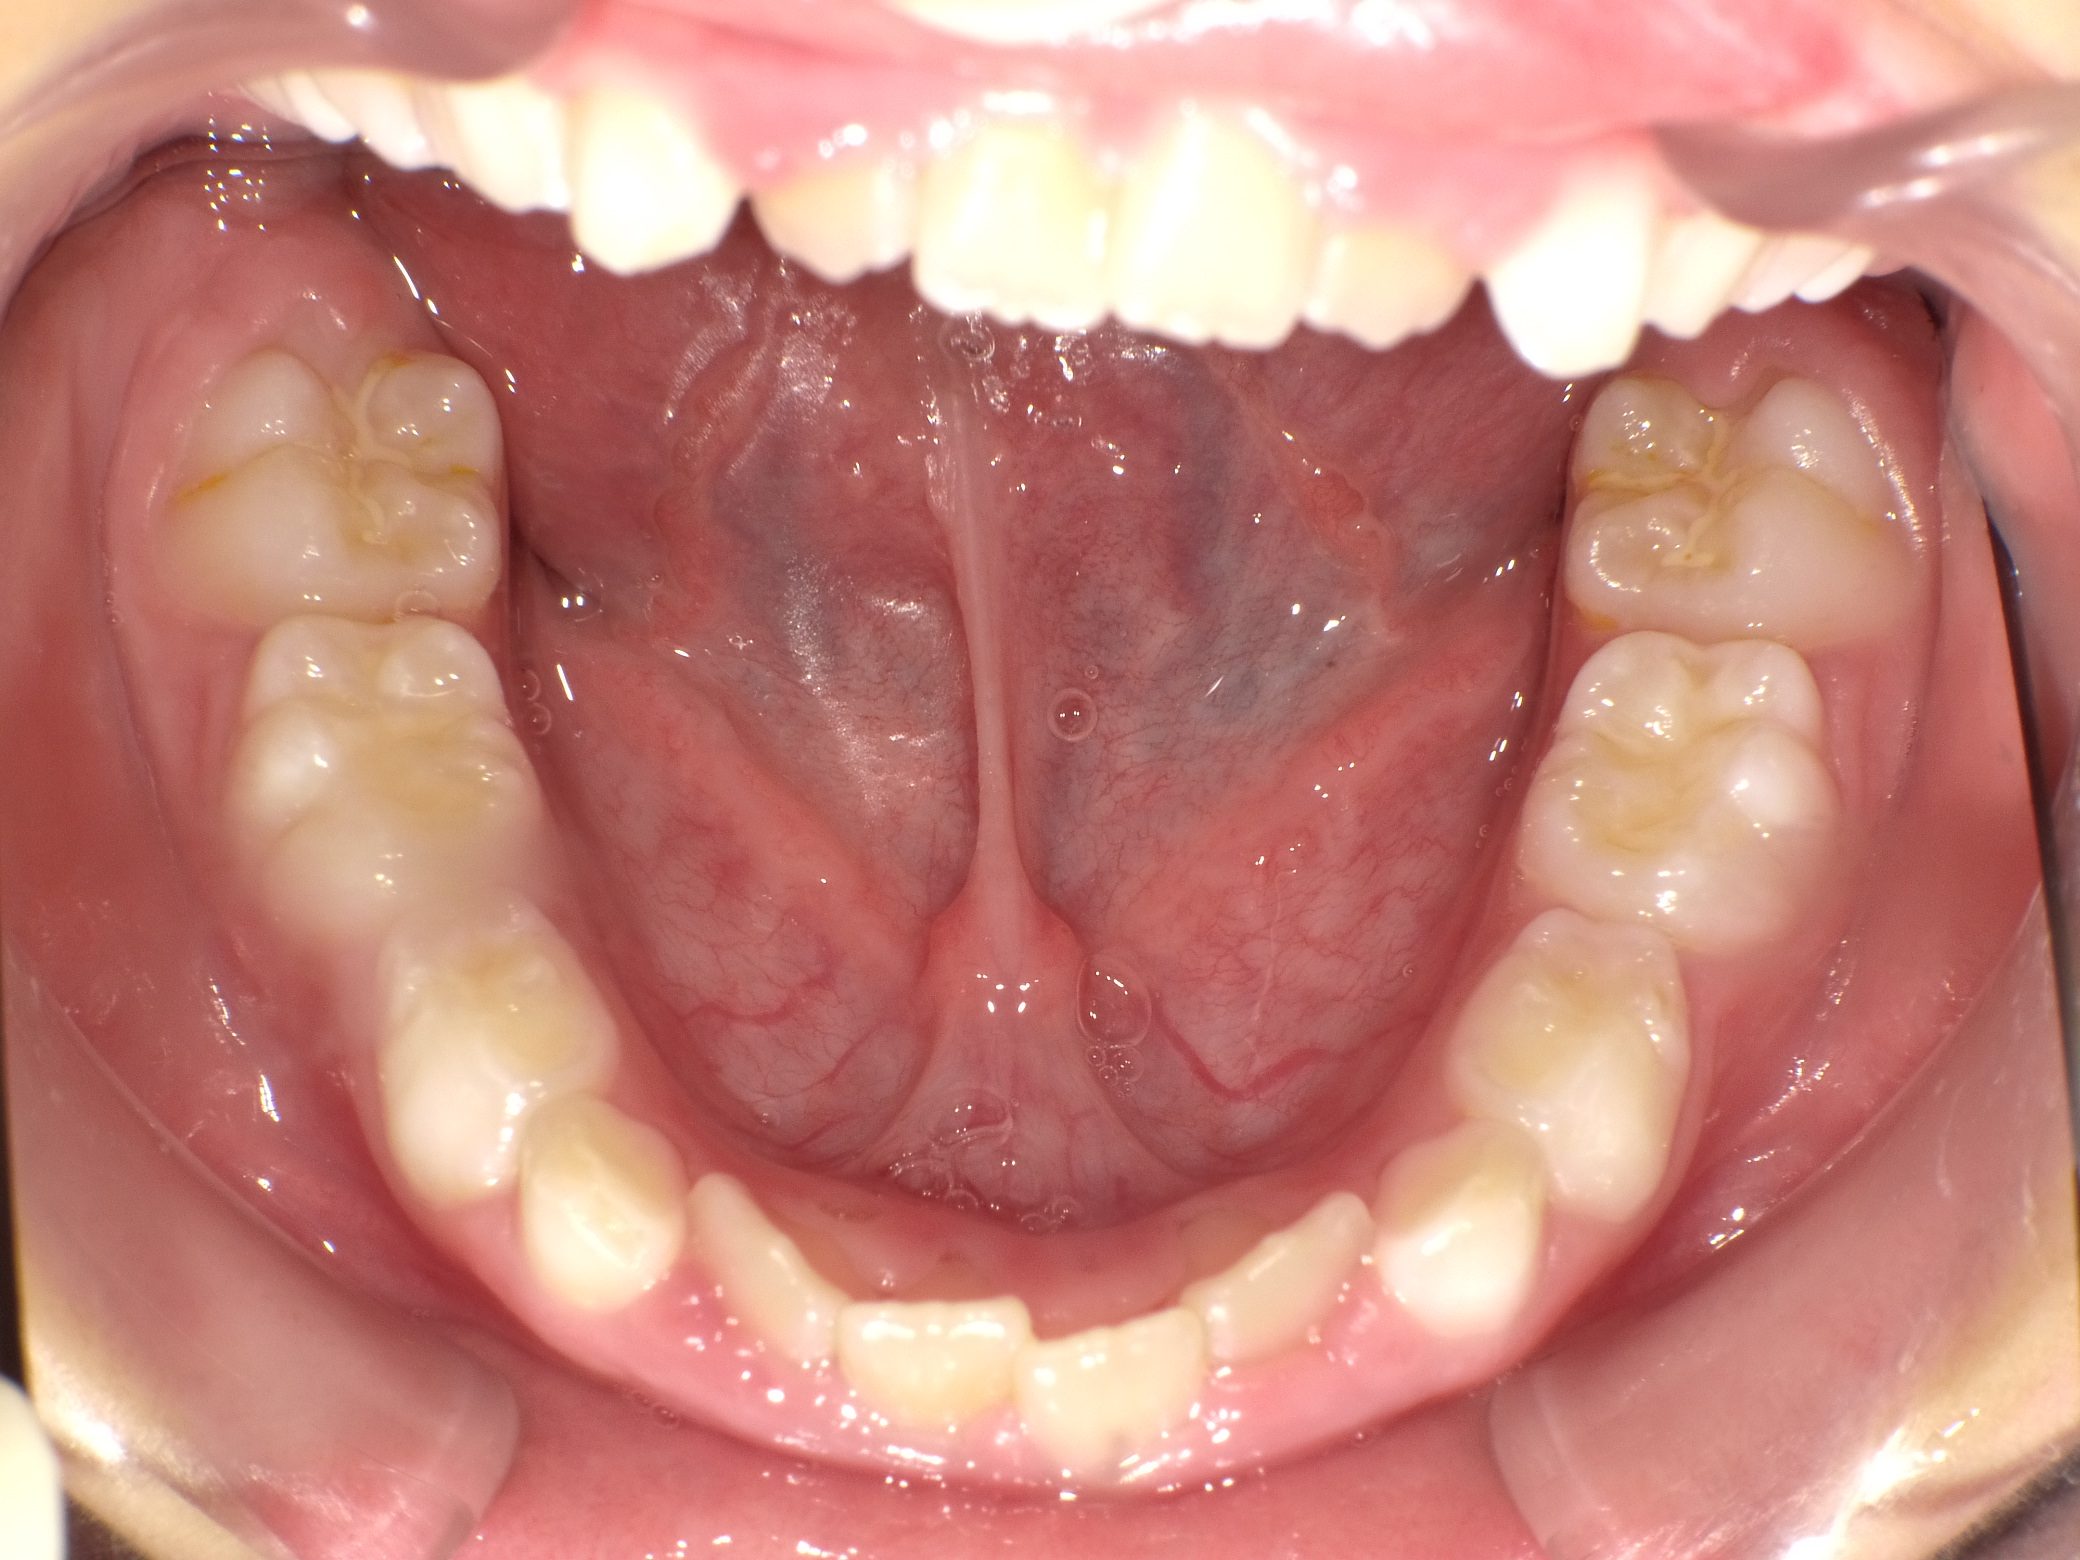

【小学生】 8歳 マイオブレース矯正 + インビザライン矯正 叢生(でこぼこ)を改善

Before

After

治療期間

3年年

治療開始

8歳

種類

マイオブレース矯正 + インビザライン矯正

使用装置

マイオブレース 3Dリンガルアーチ インビザライン

コメント

1期治療後 叢生(でこぼこ)が少し残ったので インビザラインで治しています

現在も 維持してくれています